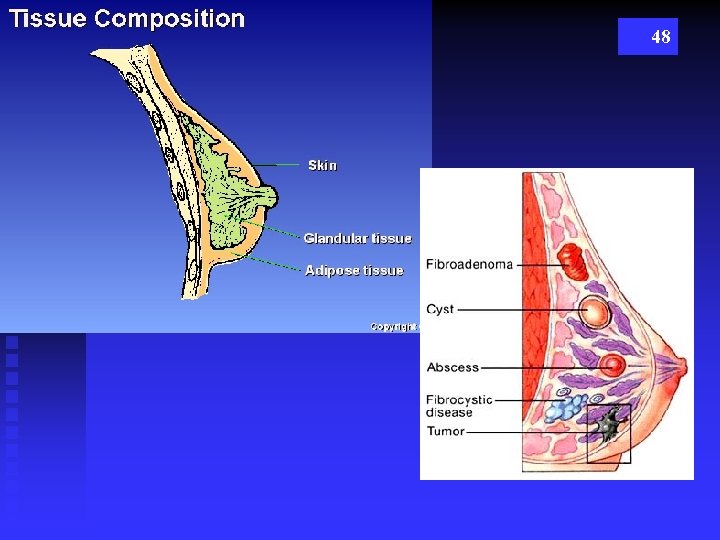

TYPES OF BREAST TISSUE GLANDULAR n DUCTS n LOBES n LOBULES n TDLU n MOSTLY SEEN UPPER OUTER QUADRANT 46 STROMAL n FATTY TISSUE n CONNECTIVE TISSUE n (COOPER’S LIGAMENTS – SUSPENSATORY LIGAMENTS

3 Tissue Types 47

48